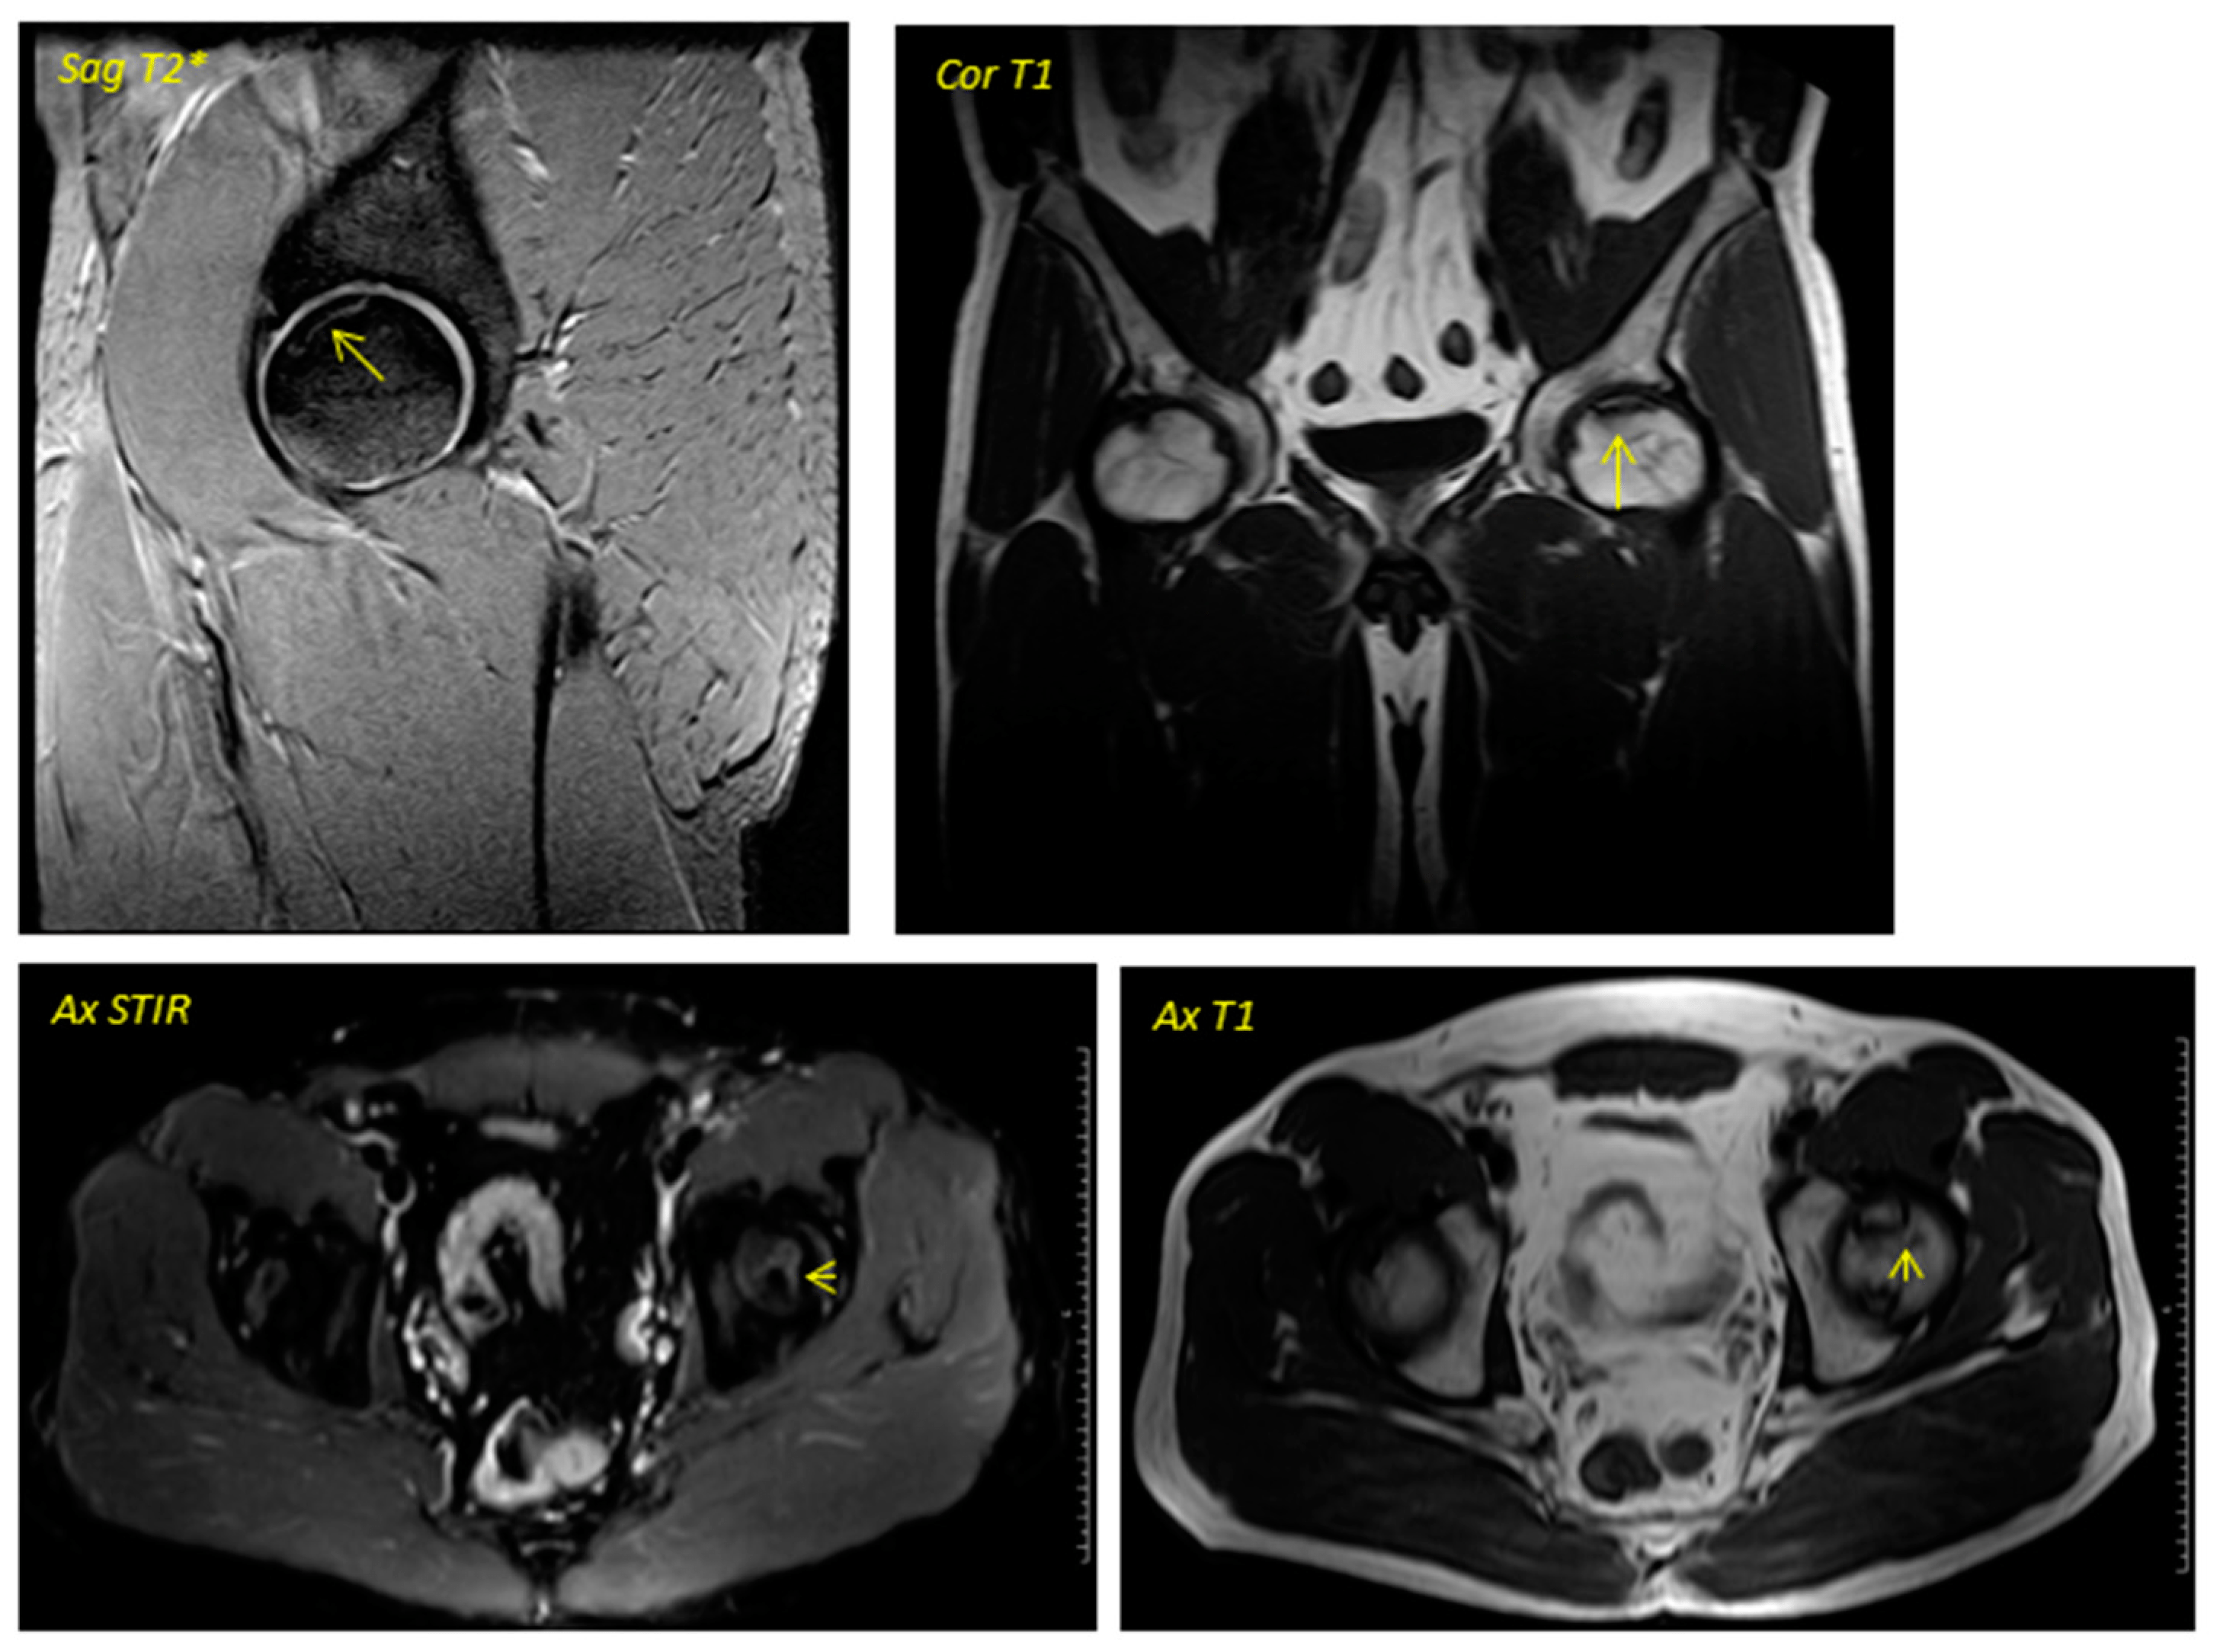

關(guān)于影像學(xué)研究,在12個月的隨訪期間,在影像學(xué)演變中觀察到了一些發(fā)現(xiàn)(圖1和圖2)。

首先,方向的變化從第六個月開始出現(xiàn)在所有病例中,而在早期階段并不明顯。其次,62.5%的患者 ( n=5) 在手術(shù)后的第一年內(nèi)實現(xiàn)了影像穩(wěn)定。第三,兩名患者 (25%) 出現(xiàn)壞死區(qū)進展,而一名 (12.5%) 患者出現(xiàn)明顯的再骨化跡象。盡管觀察到描述性差異,但后一個參數(shù)的p值在統(tǒng)計學(xué)上并不顯著。